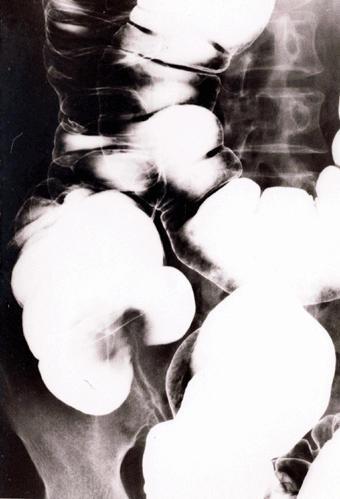

疾病(病理主体)的分类其他肿瘤/恶性阑尾粘液肿瘤

部位(按器官分)大肠/阑尾

检查方法X线

肿瘤最大直径40以上